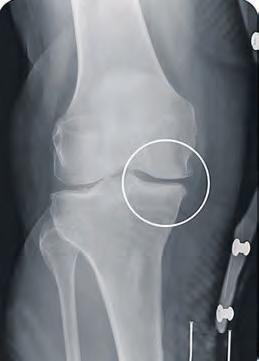

Schmerzen in den Griff bekommen

Wie Orthesen bei Arthrose das Leben erleichtern können

REGION – Wenn das Knie schmerzt, ist oftmals Arthrose das Problem. „Es gibt in Deutschland mehrere Millionen Menschen, die an der Erkrankung leiden. Die Betroffenen beobachten zum Beispiel Entzündungsschübe, Verdickungen und Verformungen an Knien, Fingern und an weiteren Gelenken“, erklärt Thorsten Belkot, Orthopädietechniker bei Oesterreich Orthopädietechnik. Betroffene könnten oftmals durch hochmoderne Orthesen, die die Gelenke entlasten und dadurch die Schmerzen reduzieren, zu einem aktiveren Alltag mit mehr Lebensqualität zurückkehren, so der Fachmann. Dabei sei es durch die gezielte Gelenkentlastung möglich, ganz normal wieder spazieren zu gehen oder auch moderat Sport zu betreiben. Oesterreich Orthopädie-Technik führt spezielle Orthesen für leichtere, aber auch für fortgeschrittene Kniearthrosen. Thorsten Belkot bietet Betroffenen die Möglichkeit, die innovativen neuen Entlastungs-Orthesen

Gelenkverschmälerung auf der Knie-Innenseite ohne Orthese.

der Firma Össur während der Arthrose-Testwochen auszuprobieren. „Die klinisch nachgewiesene Wirksamkeit sowie eine einfache Handhabung der Orthese sprechen für sich“, betont Belkot.

Als am stärksten belastetes Gelenk des menschlichen Körpers ist das Knie am häufigsten von arthrotischen Veränderungen betroffen.

Zugrichtung zur Entlastung des Gelenks auf der Knie-Innenseite.

Heilbar sind Arthrosen nicht. Es gibt jedoch effektive Methoden, um den Schmerz in den Griff zu bekommen und so eine eventuelle Operation weit hinauszuzögern.

Oesterreich Orthopädietechnik bietet vom 24. April bis 5. Mai spezielle Beratungen rund um das Thema Arthrose und kostenloses austesten einer Orthese an.

Gelenkerweiterung auf der Knie-Innenseite mit Orthese. Fotos: Oesterreich

Anmeldungen nimmt das Team unter Telefon 79 00 30 sehr gerne entgegen. Die beiden Orthesen-Testwochen finden in allen drei Bremer Filialen in der Bürgermeister-Smidt-Straße 32–36 (nähe Hauptbahnhof), Berliner Freiheit 1e (Vahr) und in Stader Straße 35 (Peterswerder) statt. Weitere Informationen unter www.ot-oesterreich.de. WR